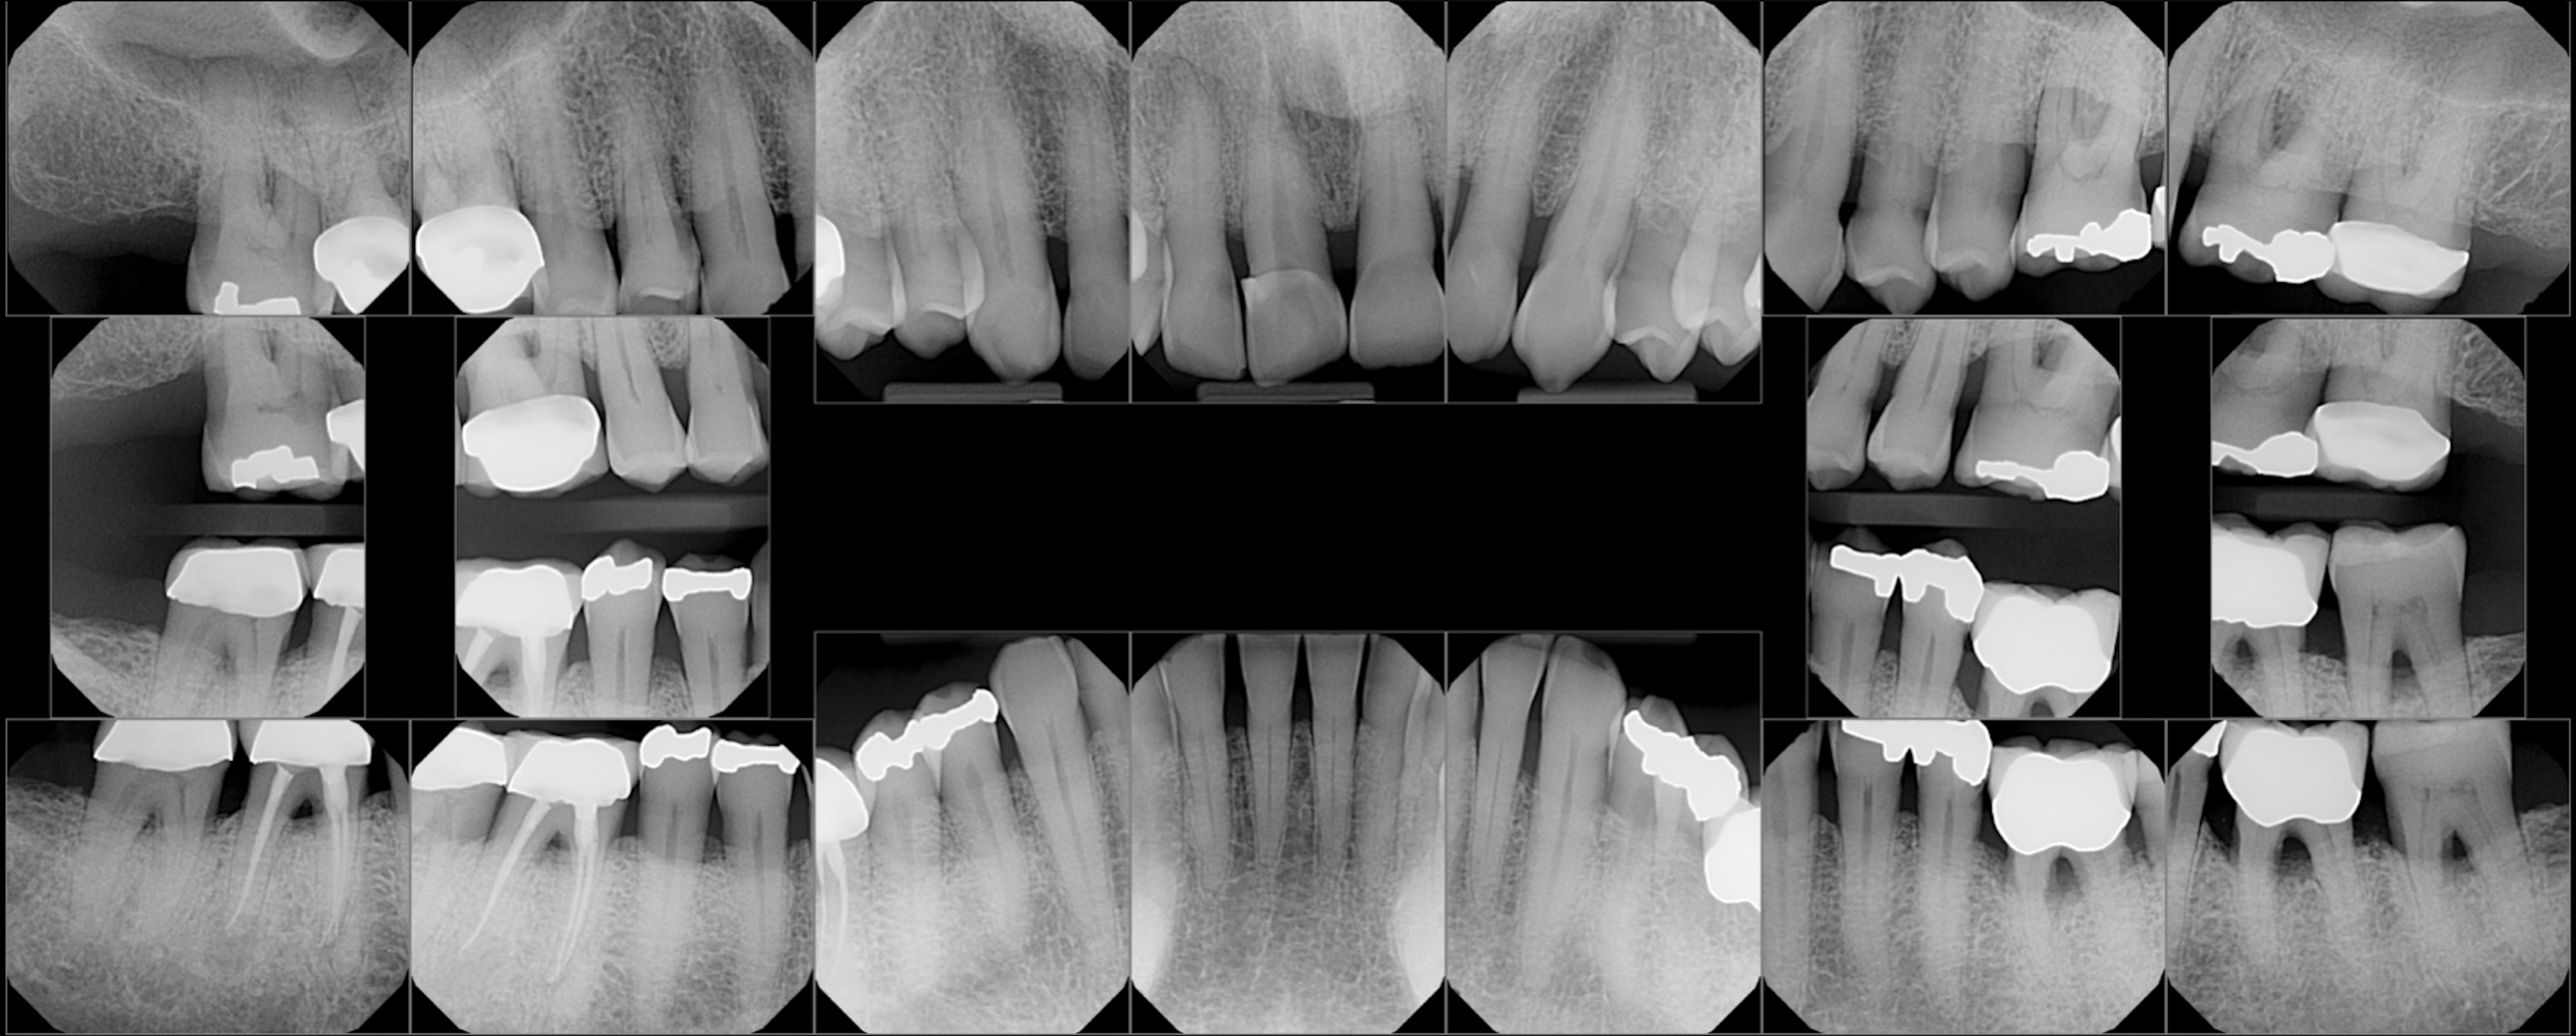

Fig 7. Pretreatment periapical radiographs.

Figure 7

Periodontal examination revealed generalized BOP and PDs up to 9 mm in the maxillary and mandibular molars with multiple furcations in each molar (Figure 2 through Figure 7). He presented with class I mobility in many posterior teeth and class II mobility in teeth Nos. 3 and 9 (maxillary right first molar and maxillary left central incisor, respectively). The periodontist decided to score tooth No. 3 for the PRS, as this was the most periodontally involved molar that was planned to be treated and maintained (Figure 2 and Figure 8). This tooth (maxillary right first molar = score 1) presented with probing depths of 7 mm (score 1); three total furcation invasions (score 3) (mesial [degree II furcation], buccal [degree I furcation], and distal [degree II furcation]); and a class II mobility (score 2). The total PRS for tooth No. 3 was 8, representing a "guarded" prognosis. Based on this score, the likelihood of not losing any teeth to periodontal disease for 15 years was 81%, and for 30 years the likelihood was just 56% (Figure 9).7

The periodontist felt that teeth Nos. 17 and 18 (mandibular left third and second molars, respectively) had a questionable prognosis due to severe periodontal attachment loss, class III furcations, and probable furcation caries as detected on radiographs. These two teeth were treated the same as the others with the patient being advised that they may need either retreatment or extraction in the future with dental implants possibly being recommended.